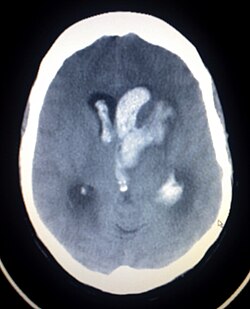

Beyin qansızması və ya Hemorragik insult — qeyri-travmatik beyin qansızması daha çox (60% hallarda) arterial hipertenziyanın fəsadı kimi baş verir. Hipertenziv beyindaxili qansızma başlıca olaraq, beynin perforasiyaedici arteriyaları hövzəsində — bazal nüvələr – (50%), talamus (15%), beynin ağ maddəsi (15%), körpü (10%) və beyincik (10%) hövzəsində lokallaşır. Beyin qansızmasının başqa bir səbəbi aretriovenoz malformasiyanın (AVM) yırtılması və ya kisəli anevrizmadır. AVM zamanı hematomalar əsas baş beyinin ağ maddəsində və ya bazal nüvələrdə lokallaşır. Ahıl yaşlarda əsas səbəb isə amiloid angiopatiyası hesab olunur.